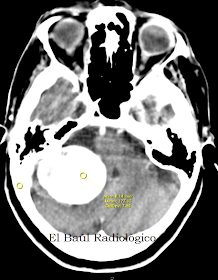

FIGURA 6-E) Control postquirúrgico inmediato. En la imagen de TAC se aprecia la zona de craniectomía y la extirpación del schwannoma (flecha roja)